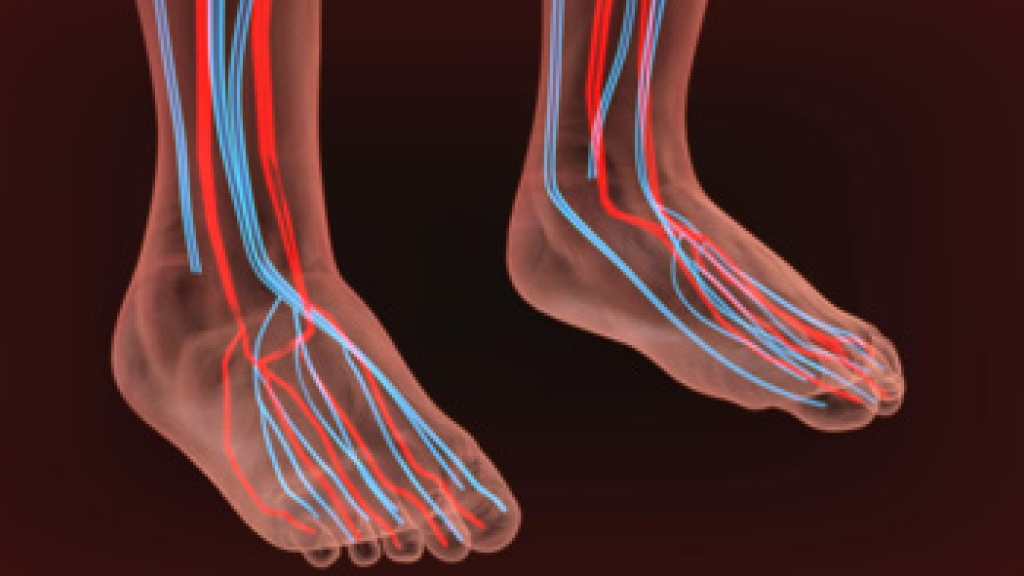

Preventing falls at work is essential for safety and productivity. Workers should stay alert to hazards in their work areas, paying attention to conditions that may create risks. Parapet walls, ladders, and warning lines are in place to provide physical protection and help guide safe movement, but they are most effective when you actively use them as intended. Ask for training so you have the knowledge to recognize potential dangers, move through the workspace safely, and handle equipment the right way. By staying aware and applying training, you can protect yourself while completing tasks efficiently. Despite these measures, accidents can still happen, leading to foot and ankle injuries such as sprains, fractures, or tendon damage. These injuries can cause lasting pain and limit mobility, if not treated properly. A podiatrist can diagnose and provide effective care to restore function and prevent long-term complications. If you have sustained a foot or ankle injury from falling at work, it is suggested that you consult a podiatrist who can treat various foot conditions, and guide you on additional fall prevention tips.